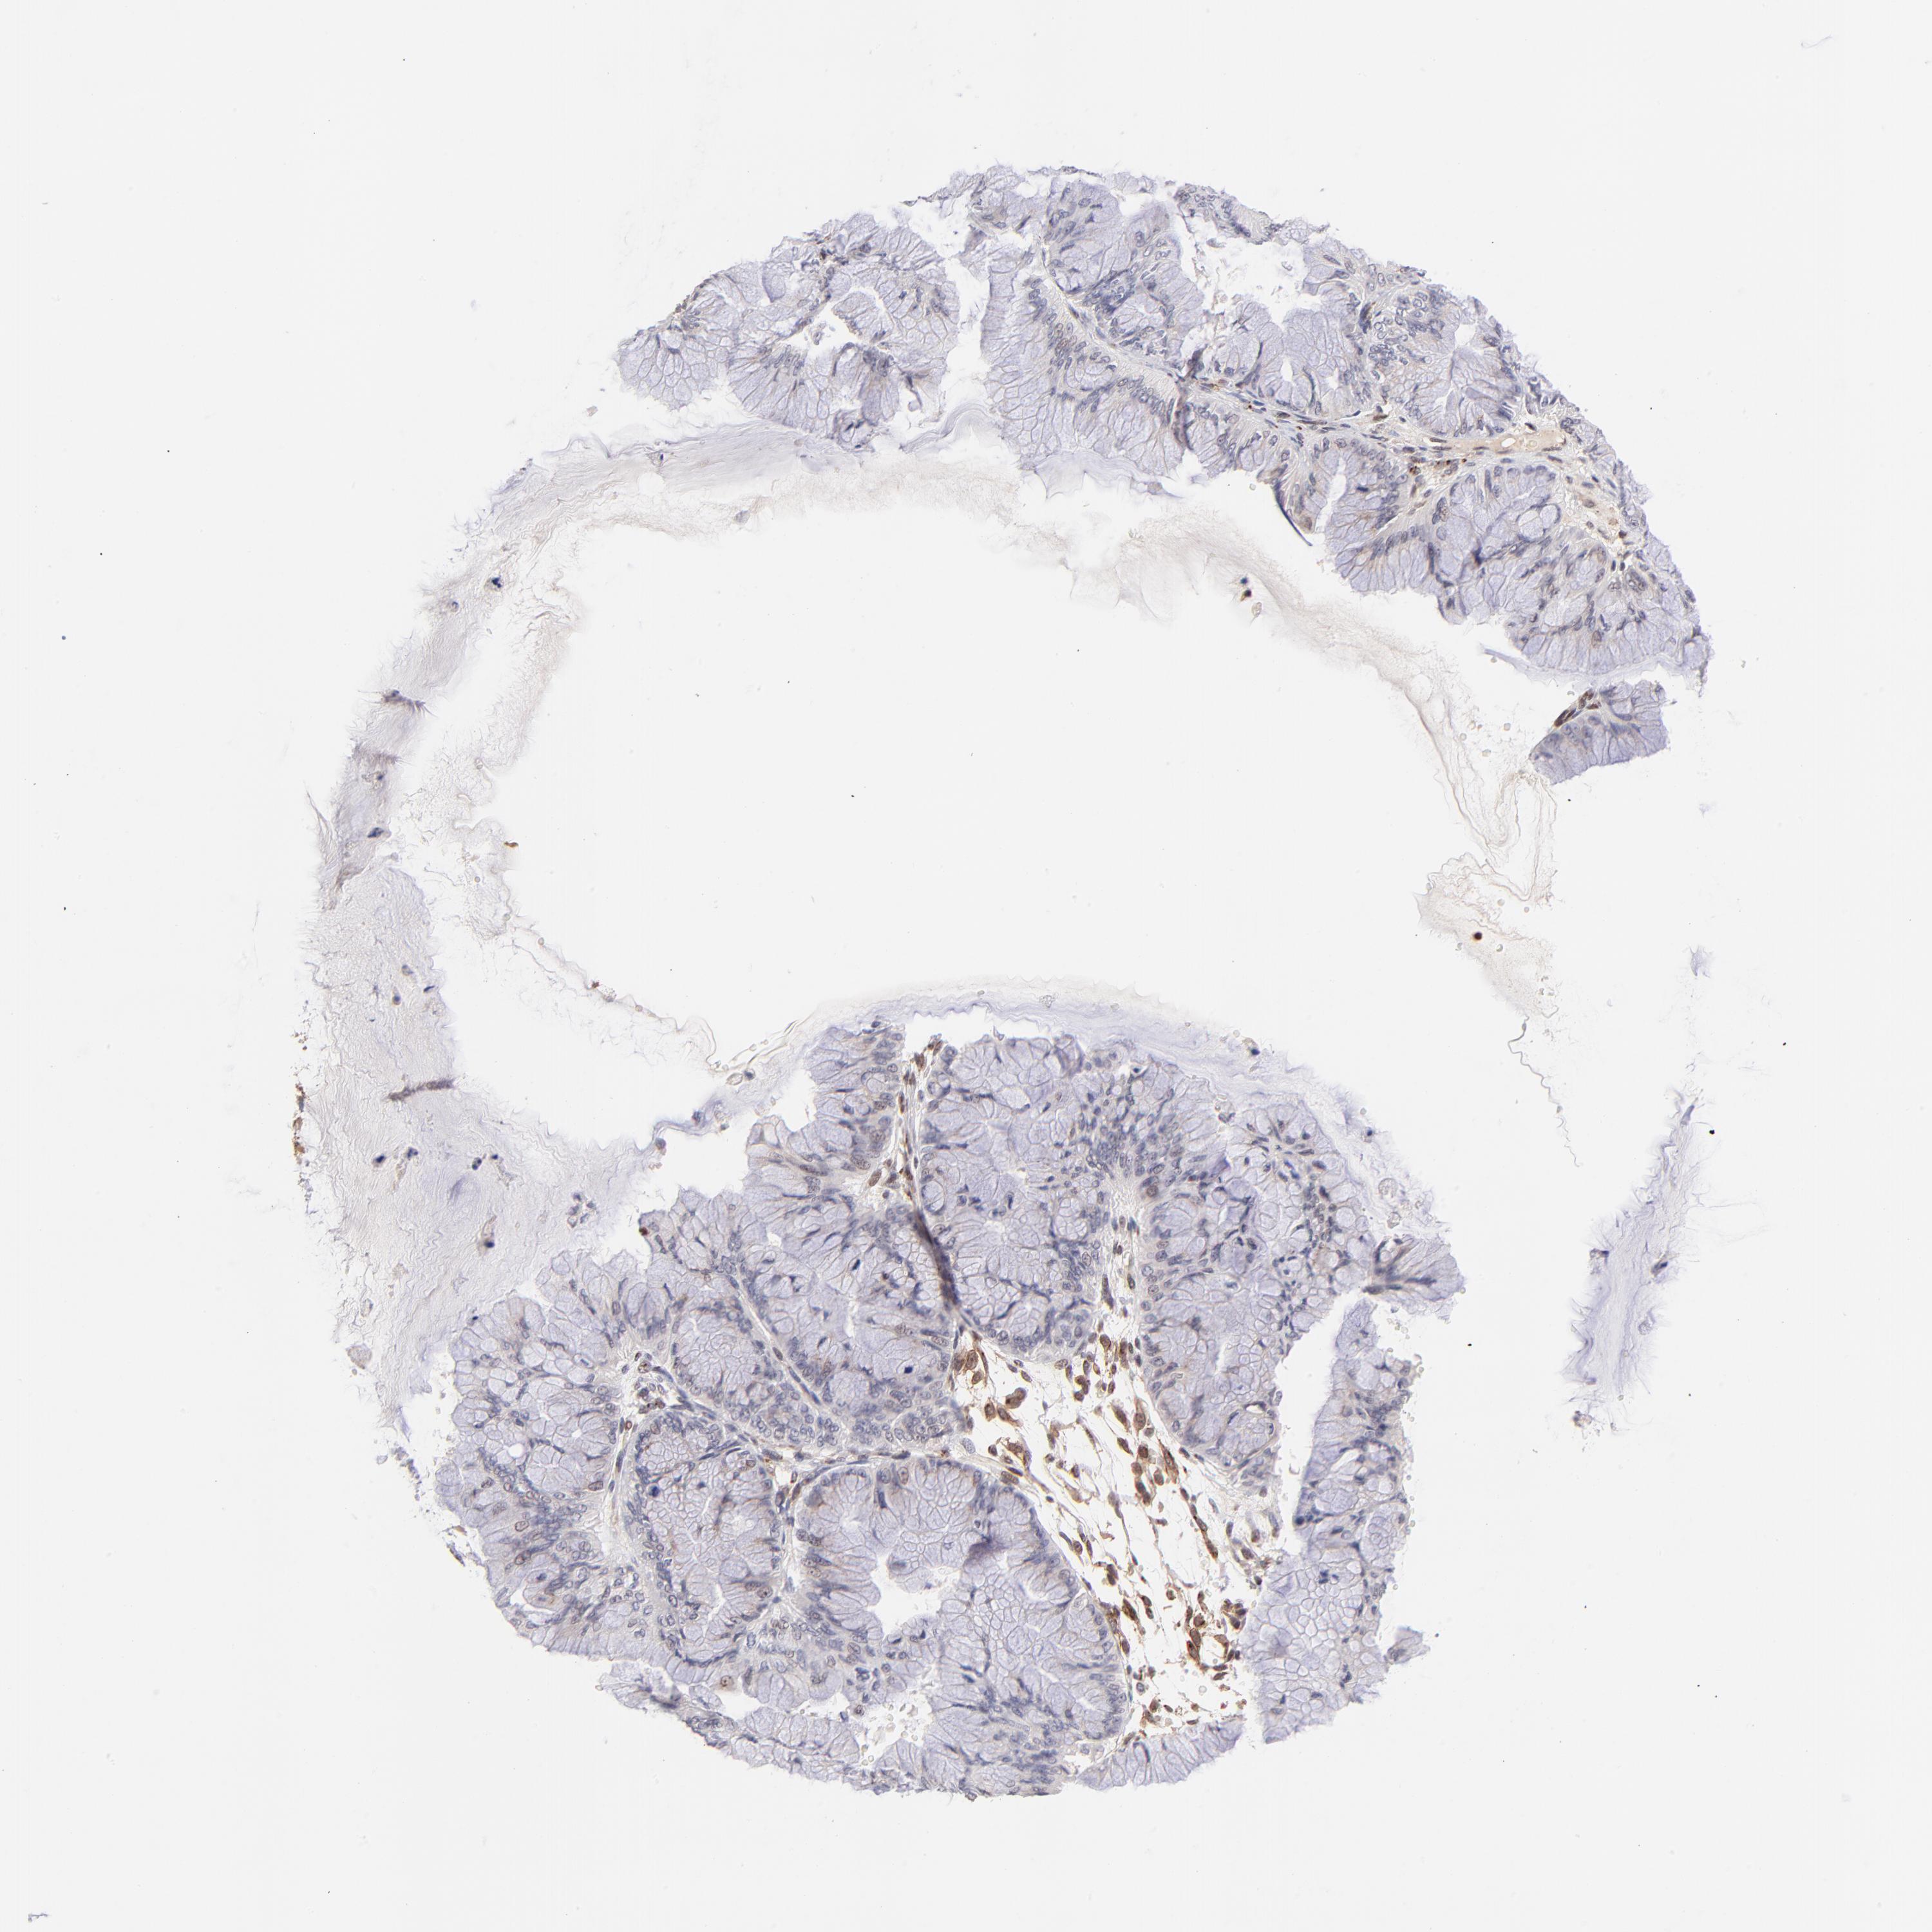

OVARIAN CANCER - Protein expressioni

A mouse-over function shows sample information and annotation data. Click on an image to view it in a full screen mode. Samples can be filtered based on level of antibody staining by selecting one or several of the following categories: high, medium, low and not detected. The assay and annotation is described here.

Note that samples used for immunohistochemistry by the Human Protein Atlas do not correspond to samples in the TCGA dataset.

Antibody stainingi

Antibody staining in the annotated cell types in the current human tissue is reported as not detected, low, medium, or high, based on conventional immunohistochemistry profiling in selected tissues. This score is based on the combination of the staining intensity and fraction of stained cells.

Each image is clickable and will lead to virtual microscopy that enables deeper exploration of all samples and also displays staining intensity scores, fraction scores and subcellular localization as well as patient and tissue information for each sample.

Antibody HPA003184

Antibody HPA003185

Staining

High

Medium

Low

Not detected

Intensity

Strong

Moderate

Weak

Negative

Quantity

>75%

75%-25%

<25%

None

Location

Nuclear

Cytoplasmic/membranous

Cytoplasmic/membranous,nuclear

Cystadenocarcinoma, mucinous, NOS

Carcinoma, endometroid

Cystadenocarcinoma, serous, NOS